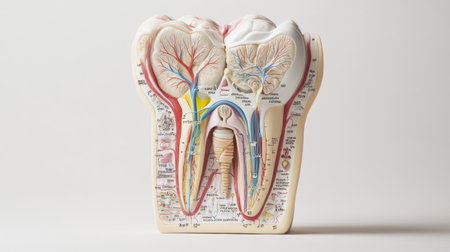

Detailed anatomical model showing human tooth structure, emphasizing root canal system. Ideal for educational purposes in dental hygiene and anatomy studies.

A close-up view of an anatomical model of a human molar tooth's cross-section. The white enamel cap transitions to yellow dentin, revealing the red pulp chamber and root canals within. The surrounding bone structure is depicted with porous texture in beige and red hues. The background is a solid, deep blue.

Detailed depiction of a tooths anatomy highlighting its internal structure and layers.

Tooth model displaying its complex internal structure including enamel, dentin, pulp, and root canals, standing against a vibrant background of colorful, out of focus lights

This image presents a detailed anatomical model of a human tooth, highlighting its layers in a contemporary dental environment for educational purposes.

Dental tooth cross section model showing enamel, dentin, pulp, gum and root structures against a soft colorful bokeh background for oral health education and dentistry study

A detailed dental model illustrates the anatomy of a human tooth highlighting its inner structure including roots and nerves. This model is used for educational purposes in a dental clinic.

This image depicts a detailed anatomical model of a human tooth, showcasing the intricate internal structures, including nerves and blood vessels, essential for educational and healthcare purposes.

Transparent tooth model displaying detailed internal anatomy, including nerves, blood vessels, and pulp structure, isolated on a gray background.